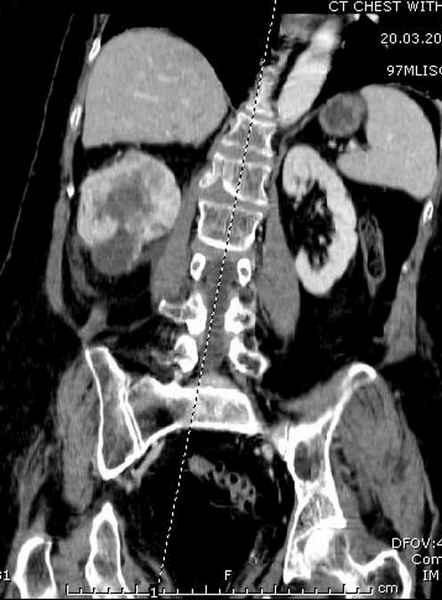

Со слов, больная ничем не болела, только последние 3 месяцев чувствовала боли в бедренной области. КТ брюшной полости подтвердил увеличенную правую почку. (5-6)

Для предупреждения кровотечения во время рассверливания, за день до операции провели эмболизацию сосудов питающий метастаз. http://radiology.rsnajnls.org/cgi/reprint/150/3/673.pdf (7-11, 12-15-16)

С минимальным рассверливанием и ретроградным методом провели остеосинтез бедра 12 мм гвоздем. (17-20)

Кровопотеря во время операции меньше 100 мл.